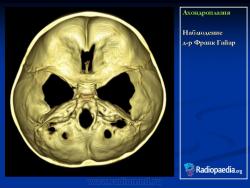

Наблюдение д-ра Франк Гайар

Ахондроплазия

http://radiopaedia.org/images/392220

http://radiopaedia.org/cases/achondroplasia